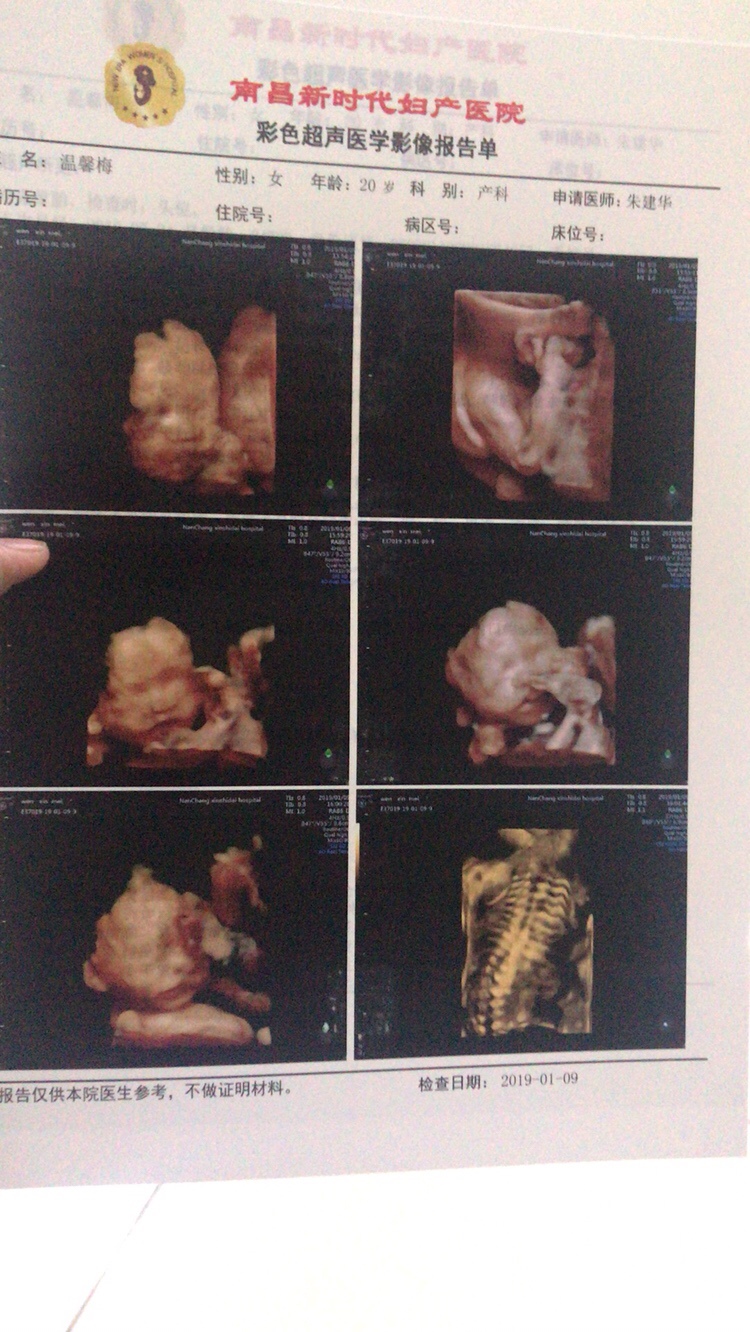

孕14周+1天

孕14周+5天